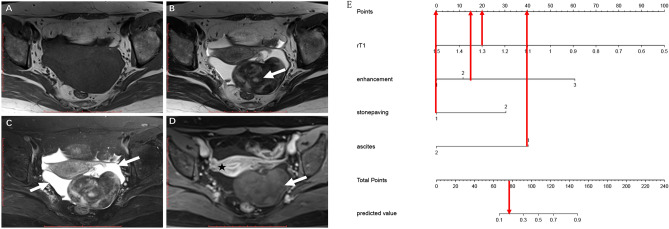

A nomogram was constructed based on the multivariate logistic regression results of Model 3 (Fig. 3A). The calibration curve (Fig. 3B) of the nomogram showed that the calibration between the predicted and actual outcomes of tumor identification was good. DCA analysis showed that the nomogram was clinically useful, with a high net benefit over a wide range of threshold levels (Fig. 3C). Figure 4 shows a representative case of the OF group, whereas Fig. 5 shows a representative case of the BLM group.

Figure 4.

A 65-year-old woman with an OF. (A) Axial T1-weighted imaging shows a hypointense tumor in the left ovary. (B) On T2-weighted imaging, the tumor exhibits the cystic part (white arrow). (C) On the fat-saturated T2WI, the free ascites (white arrow) were seen in the pelvis. (D) The tumor showed mild contrast enhancement (white arrow) comparing with the uterus (asterisk). (E) This tumor’s total score is 75 (r-T1 = 23, enhancement = 12, stone paving = 0, ascites = 40) with a predicted value of 0.15 calculated by the nomogram, the corresponding probability of OF is 85%.